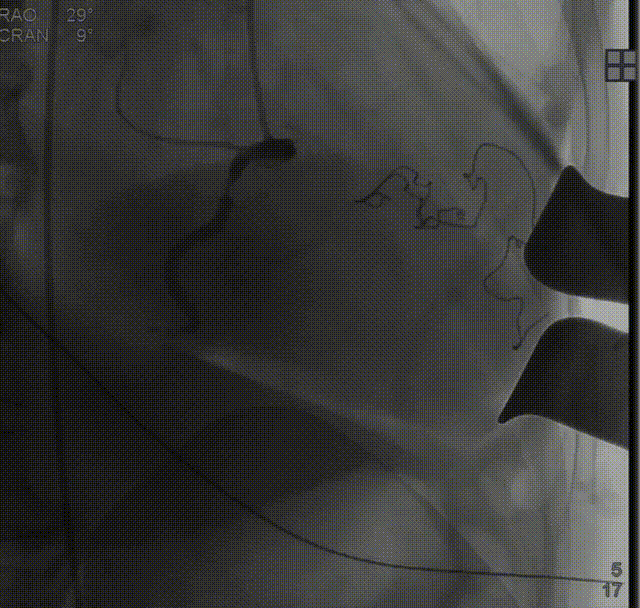

经股动脉送入猪尾导管,行根部造影:

定位件入窦后造影:

降落瓣膜件,完成释放:

复查根部造影,未见明显反流: